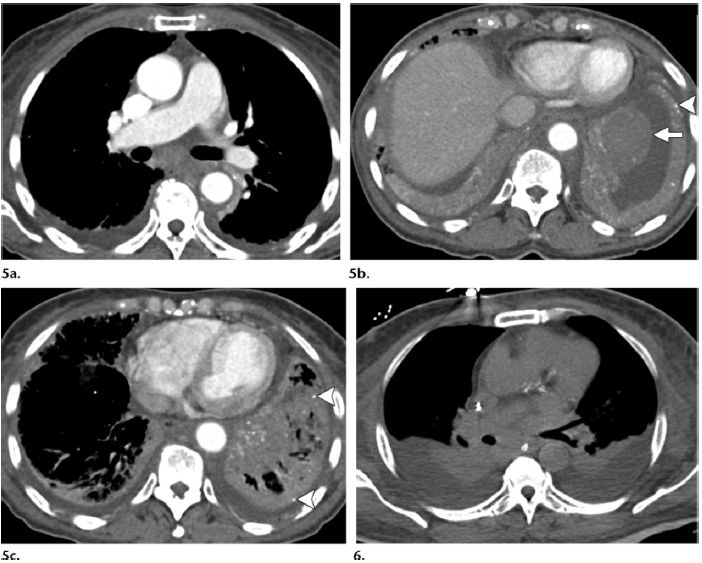

图5, 6 (5)患者,女,70岁,系统性淀粉样变性(AL)累及肺、胸膜及纵隔。(a)增强CT示气管隆突下淋巴结肿大。(b,c)左下叶肿块为淀粉样蛋白沉积物。斑点状实质钙化(图b和c箭头)也见于肺实质淀粉样变性。双侧胸腔积液

(图c),胸穿证实了胸膜淀粉样变性。(6)患者,男,63岁,多发骨髓瘤

及淀粉样变性。肺CT平扫

示双侧少量胸腔积液及气管隆突下淋巴结肿大。尽管无特异性,淋巴结为含淀粉样蛋白沉积物。